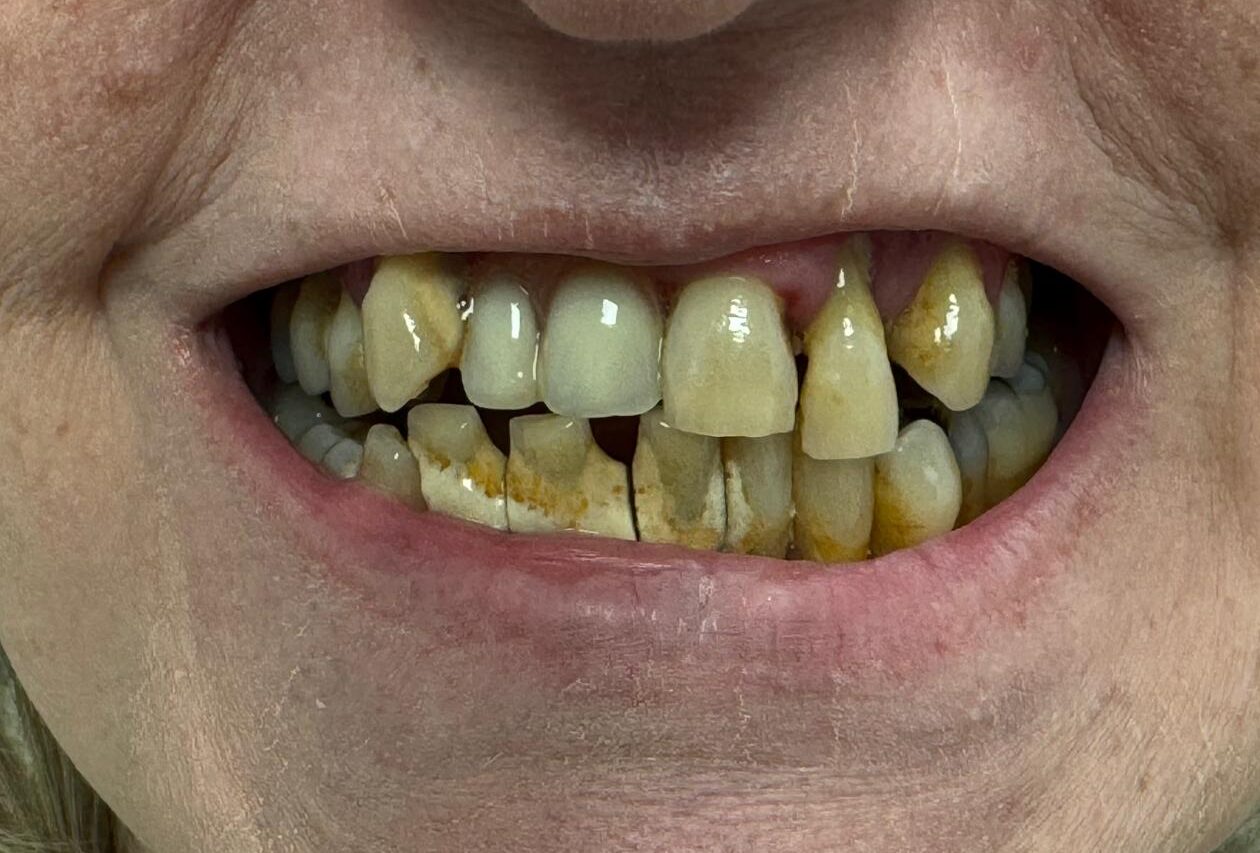

Full Arch on 5 Implants

'All on X'

Before

After